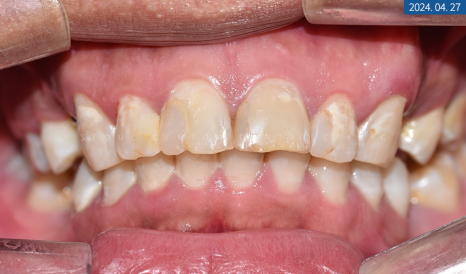

환자분의 #14, #24 인공치를 만들면서 중간에 전치부 라미네이트도 진행했는데요. 자연치와 유사한 색상을 구현하기 위해 쉐이드 가이드도 대조했으며 최소 치질 삭제 후 인상 체득을 했습니다. 동일하게 기공소에서 얇은 도자기 소재 판이 만들어져서 치과용 접착제로 틀어짐 없이 정확하게 붙여드렸답니다.

마무리된 앞니를 보면 전과 다르게 깨지고 갈라진 크랙 없이 단정하고 밝은 느낌이 들게 되었습니다.